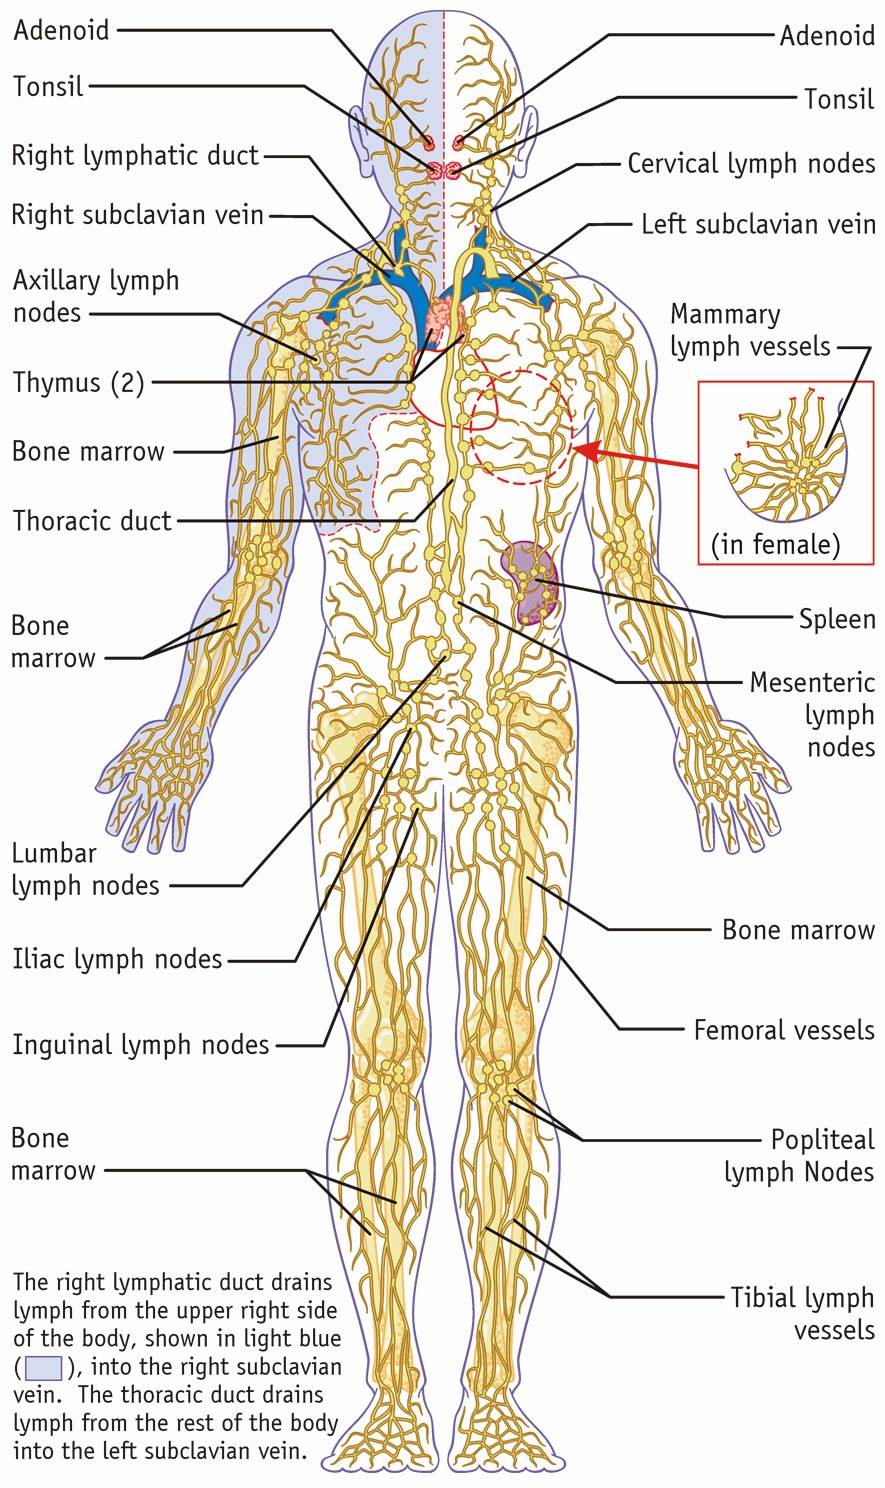

Map Of Lymph Nodes In Human Body

mungfali.com

mungfali.com

7. The Lymphatic System - SimpleMed - Learning Medicine, Simplified

www.simplemed.co.uk

www.simplemed.co.uk

lymph lymphatic nodes

Lymphatic System

biology-diagrams.blogspot.com

Lymphatic System | Structure, Function, & Facts | Britannica

www.britannica.com

www.britannica.com

lymphatic britannica organs vessels lymphocytes